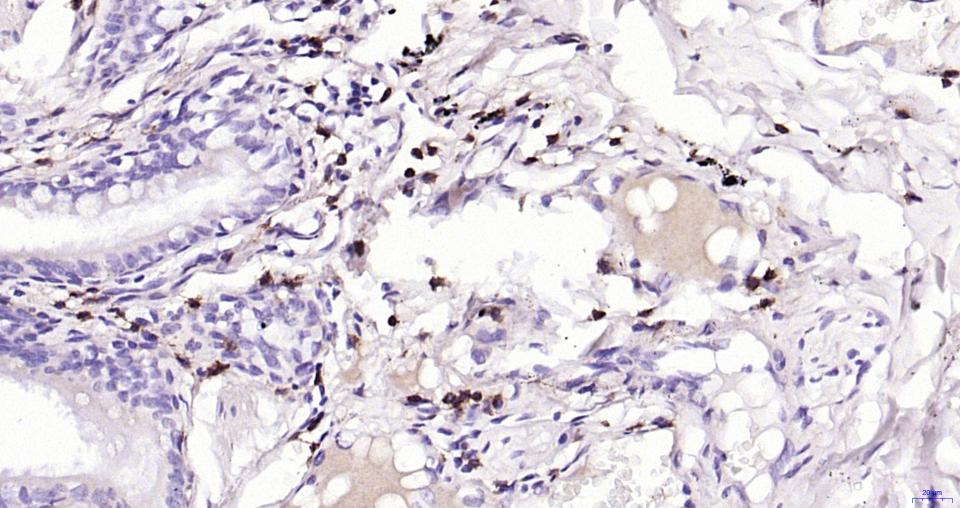

| IHC-P | Human | 1:100-500 | |